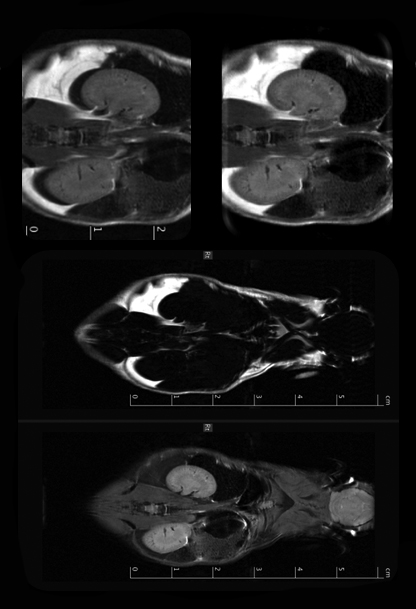

无线心脏功能评估

IntraGateUTE 可在15分钟内实现平面分辨率为(130×130) μm²的全面心脏评估,每个心脏跳动可获得14个电影帧。

心脏模型的一个共同特点是其不稳定性。因此,调查速度对动物福利至关重要。使用IntraGate可以节省宝贵的设置时间,因为它不需要任何电极。这种独特的方法,记录所有的心脏帧,而不需要触发,与IntraGateUTE中的UTE相辅相成,与传统方法相比,可加速8倍。流动伪影最小化,便于使用自动心脏分析软件进行简化评估。